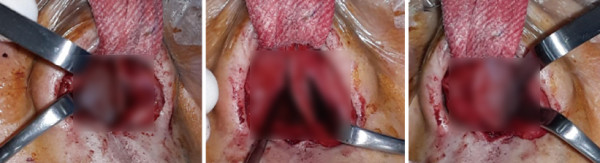

1997년생 남자 환자가 지속적인 코막힘과 콧물을 증상으로

내원하였다. 양악수술과 코 필러 및 실 삽입 수술이력이 있었다. 수술 전 이학검사상 좌측에서 우측으로 의 역C형 사비가

보였으며 비주와 비공의 비대가 관찰되 었다

수술 전 사진. 역C형 사비와 흡기 시 우측 비익연골의 허탈이 확인되었다.

비주와 비공의 비대칭도 보였다

수술 전 CT. 비중격 만곡이 보였다. 골부와 연골부의 좌측 만곡과 spur가 관찰되며 전체적으로

C-shape deviation이 확인되었다. 비중격 만곡으로 인해 측면에서 비중격의 음영 소실도 보였다.

Cottle test에서는 좌측에서 positive가 관찰되 었으며, 흡기 시 우측 비익연골의 허탈이 관찰되었다. 내원 당시 시행한 CT상 비중격의 골부와 연골부 상단에서 좌측으로 만곡된 C-shape deviation이 확인되었다.